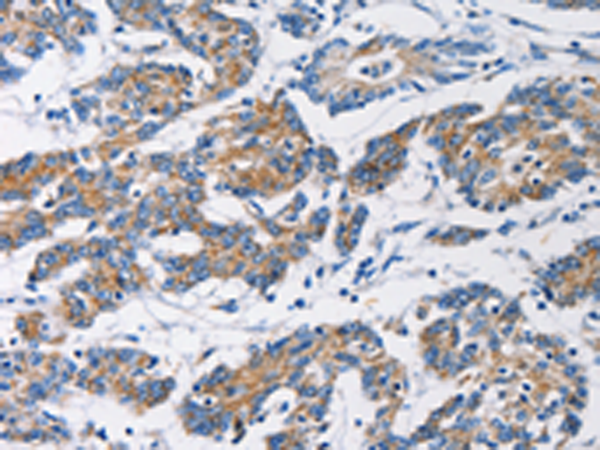

分类: 科研抗体货号: P08006别名: UCHL2; hucep-6; HUCEP-13应用: WB,IHC反应种属: Human, Mouse, Rat

分类: 科研抗体货号: P07971别名: TYRRS; CGI-04; MLASA2; MT-TYRRS应用: WB,IHC反应种属: Human, Mouse, Rat

分类: 科研抗体货号: P07989别名: FAK; FADK; FAK1; FRNK; PPP1R71; p125FAK; pp125FAK应用: WB反应种属: Human, Mouse, Rat

分类: 科研抗体货号: P07987别名: HKD; HKI; HXK1; HMSNR; HK1-ta; HK1-tb; HK1-tc应用: WB,IHC反应种属: Human, Mouse, Rat